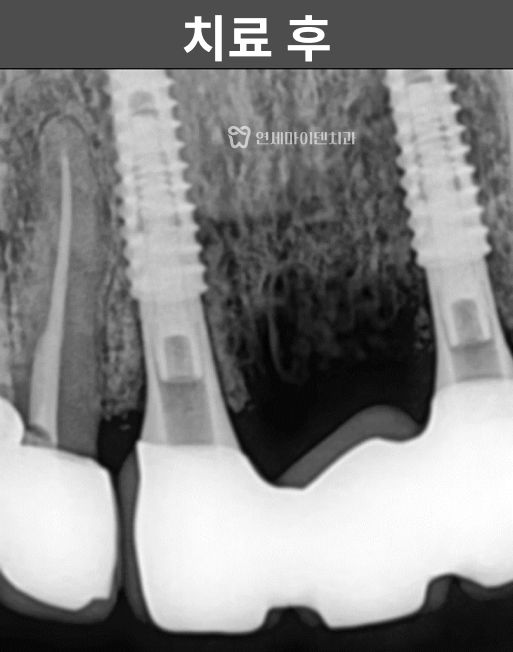

정밀 촬영 결과

두 개의 앞니 뿌리 끝, 즉 치근단 부위에서

뚜렷한 염증 소견이 확인되었습니다.한쪽 치아는

뼈 손상이 심해 예후가 불량한 상태였고,

다른 한쪽은

염증이 국소적으로 제한되어 있어

신경치료 후 경과를 지켜볼 수 있는 상황이었습니다.이에 따라 치료 계획은 다음과 같이 세웠습니다.

임플란트로 치료한 앞니는

안정적으로 자리 잡았고,신경치료를 시행한 치아는

치근단 낭성 병변이

자연스럽게 치유되면서

추가적인 치근단 수술 없이

회복을 확인할 수 있었습니다.

최종 보철을 통해

기능과 심미성을 모두 회복했으며,해당 케이스는

치료 후 3년이 지난 현재까지도

안정적으로 유지되고 있습니다.